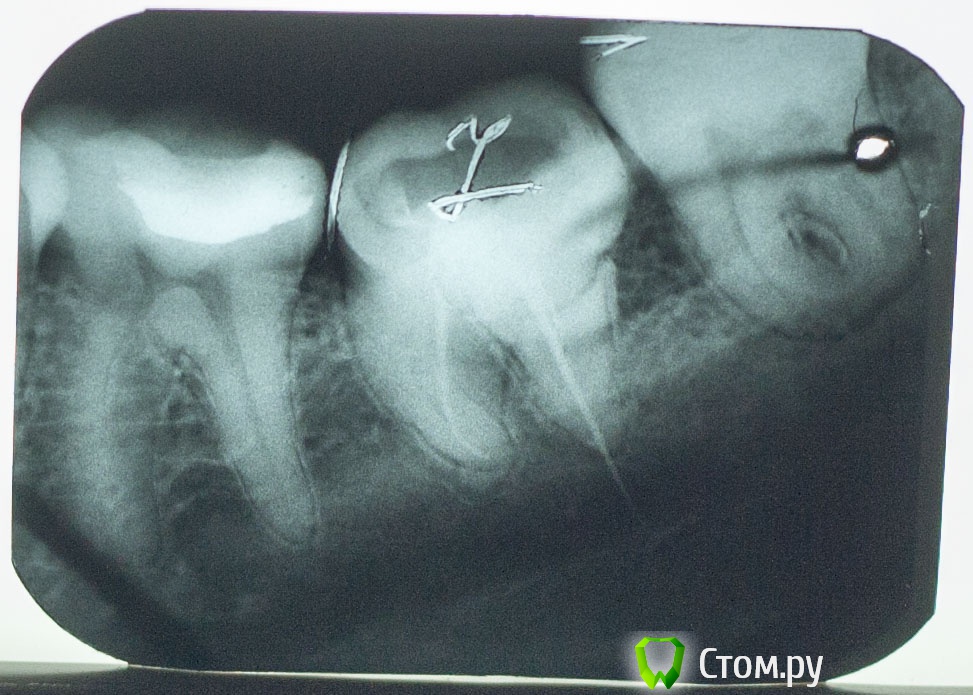

Vlad74 Опубликовано 15 января, 2014 Поделиться Опубликовано 15 января, 2014 Добрый вечер, прошу помощи. 2 месяца назад был пульпит, долго не могли определить какой зуб, ходил 2 недели в поликлинику. В итоге вроде нашли зуб 7 нижний (проводили электроодонтодиагностику показания 60, вроде бы немного болел при накусывании и постукивании), заложили мышьяк. Через 3 дня достали. Легче не стало. Через неделю болела вся левая половина верхней и нижней челюсти, наконец определили пульпитный зуб ( 5 сверху), в течении неск дней полностью запломбировали, 5 сейчас не беспокоит. Вопрос по 7 зубу. Снимок до лечения №1. Лечил в платном кабинете. Прочистили, запломбировали 1 канал, сказали остальные 2 непроходимы, поставили какую то пасту, неделю ходил с временной пломбой, боли не было. Далее поставили постоянную. После этого заболел зуб, сильная пульсация. Сделал снимок (№2), был в шоке как сделали. Через неделю обратился по гарантии. Вскрыли, заново прочистили 2 канала, поставили лекарство на неделю. Боли не было. Далее запломбировали 2 канала - 1 штифтами, 1 пастой. Сказали есть перфорации в коронковой части, заделали цементом. 3 канал не нашли, долго искали! Направили к другому врачу этой же клиники, по снимку определила ПЕРЕЛОМ корня зуба и однозначное удаление. Сейчас зуб под временной пломбой, часто напоминает о себе, реагирует на постукивание, при накусывании, немного на холод. Обратился еще к 2 стоматологам в другие клиники за советом, 1 сказал что перелома нет и нужно искать канал, 2 что каналы непроходимы и удаление. Текущий снимок №3. Пожалуйста, посоветуйте стоит ли пытаться продолжать лечение и что делать, если не найдут канал? ЗЫ Зуб значительно наклонен в сторону языка, боковая стенка зуба располагается примерно посредине жевательной поверхности соседних зубов. Спасибо Ссылка на комментарий